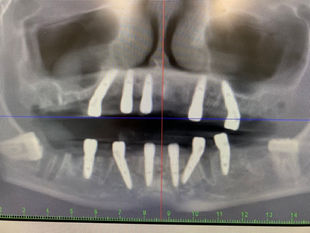

Clinical Case: Full-Arch Rehabilitation using GDT Multi-unit abutments

Clinical case presented involves the restoration of full arches in both the maxillary and mandibular regions using GDT Multi-unit abutments